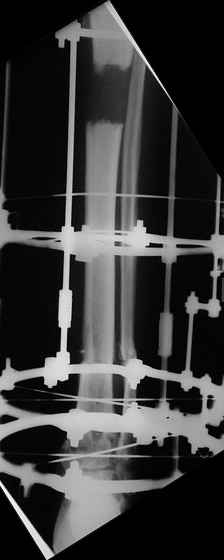

Открытый перелом- пхо+стержневой аппарат-штифтование. Через 4 месяца отек, температура 39….

Удален штифт-резекция+билокальный остеосинтез. Выращивание дистракционного регенерата

Повторное штифтование с рассверливанием. Оставлен дистально «легкий» аппарат для создания компрессии сближенных опилов на 4 недели.